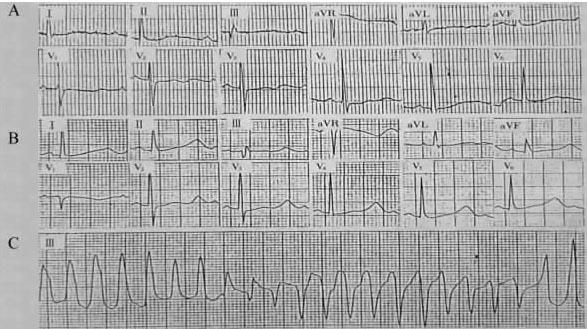

图5-1-3 低血钾致尖端扭转型室速

3.传导阻滞 可表现为房室或束支传导阻滞,见图514~517。心电图动态观察可见Ⅰ~Ⅲ度房室传导阻滞呈瞬间互变的特点,一次心电图检查不能反映病情的严重程度,故需持续心电监测。研究并显示,血清钾降低程度与房室传导阻滞程度不相平行,系钾对心肌细胞电生理的影响主要取决于细胞内外钾离子浓度之比值,而与血清钾绝对值关系较小。临床发现,随钾剂补充后,血清钾浓度的上升,房室传导阻滞逐渐改善。通常经治疗后,房室传导阻滞消失时间为2~126(6.78±13.11)小时,多数于10小时内恢复正常房室传导。伴低镁血症及酸中毒者,房室传导阻滞消失时间有较明显延长。

图5-1-4 低血钾致Ⅲ度房室传导阻滞

图5-1-5 低血钾致室内传导阻滞

图5-1-6 低血钾致完全性右束支传导阻滞、Ⅰ度房室传导阻滞

图5-1-7 低血钾致高度房室传导阻滞